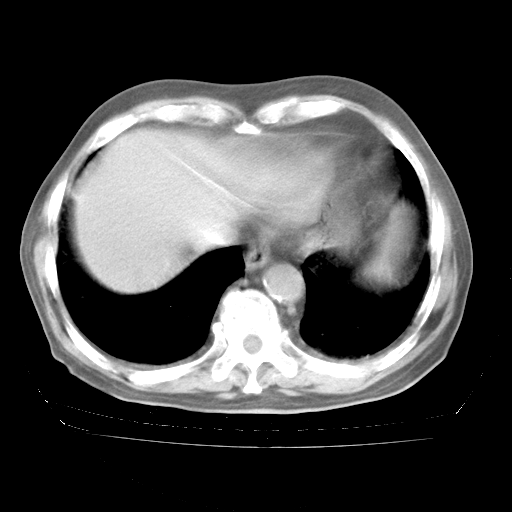

4月28日肺部CT

个人阅读4.14日肺部CT平扫:纵隔窗无异常,但肺窗示:双下肺内、后基底段有片絮状侵润影,部位以后基底段为著,以间质改变为主,呈急性肺泡炎征像,和首次住院影像学有相似之处。仅是个人读片,明日请相关专家再读片哈。其它建议同上。